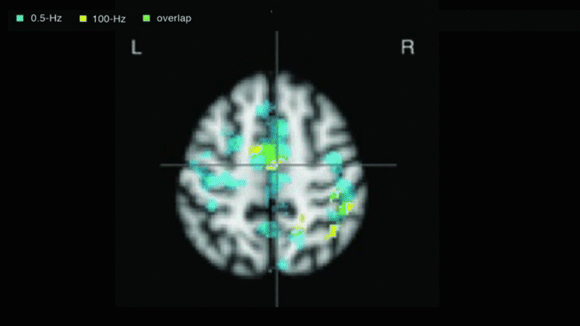

CESの信頼性は、f-MRIで確認された頭蓋神経の変化によって検証されています。CESの技術は臨床的に証明され、※FDAによって承認されています。

SleepisolのCESテクノロジーのCES(Cranial Electric Stimulation)とは、脳への刺激の一種です。

この脳への電気刺激は、電場や磁場などで使用するのと同じ量のエネルギーを使用することで、頭蓋神経系の機能を変化させます。

この刺激により、脳波の変化やホルモンの分泌量が変化します。

CESは、外耳道、上顎喉頭接合部、乳様突起、こめかみに設置された電極を通過して、脳に向かう微弱な交流電流を送信します。次に、CESは大脳辺縁系、網状体活性化系、視床下部に参加して、脳シナプスのホルモン産生に影響を与えます。

CESの治療後、セロトニン、βエンドルフィン、メラトニンなどの脳内シナプスホルモンの量が増加することが観察されています。これらのホルモンは感情をコントロールする能力や睡眠障害と深く関係しており、特にセロトニンやメラトニンの量が増えると睡眠障害に効果があることが証明されています。